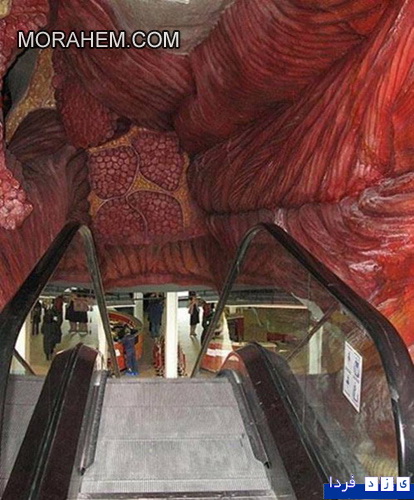

این ساختمان در هلند ساخته شده و با سفر به درون آن میتوان با بازدید از همه بخشها، از کارکرد درست یک بدن سالم آگاه شد و آموزش دید. ارتفاع این ساختمان که از نظر ظاهری پیکر انسانی نشسته است، 35 متر است.

این تصاویر عجیب و بی نظیری كه مشاهده می کنید مربوط به یك ساختمان واقع در كشور هلند است كه شبیه انسان ساخته شده و از تاریخ چهاردهم مارس 2008 برای بازدیدكنندگان فعال بوده است. بطوریکه با سفر به درون آن میتوان از تمامی قسمت ها و کارکرد درست یک بدن انسان سالم اطلاعات لازم را کسب کرد و در این تجربه جدید برای بازدیدكنندگان خصوصا دانشجویان رشته پزشکی این امکان فراهم شده بود تا با قسمتهای داخلی بدن انسان و نحوه فعالیتهای آنها از نزدیك آشنا شوند.

این بنای انسانی که از نظر ظاهری پیکر انسانی نشسته است، در كنار یك ساختمان شیشه ای با ارتفاع 35 متر بنا شده كه در جوار اتوبان A44 آمستردام به هاگو (Hague) قابل مشاهده است. گرچه این تصاویر شاید برای شما دوستان پرشین استار چندان جدید نباشد ولی آنچه مهم است اهمیت آموزش و ایجاد انگیزه برای سهولت در شناخت و درک بهتر ساختمان پیچیده و اسرار آمیز بدن انسان نسبت به نیاز محققین و دانش اندوزانی است که مایلند به گوشه ای از اسرار عظمت خلقت خداوند که همان اشرف مخلوقات است دست یابند.